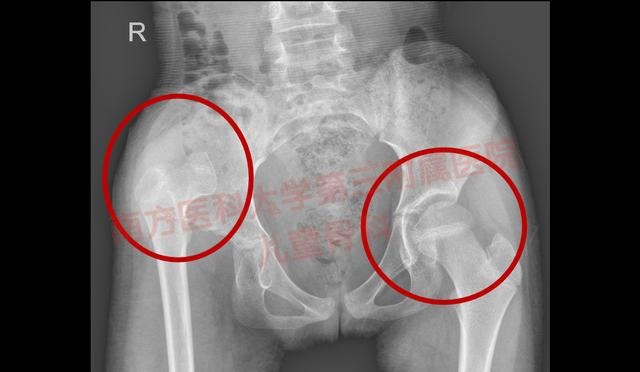

孩子长短腿7.5厘米,先天性髋关节发育不良导致跛行的原因是什么

这个小女孩9岁多了 , 她的妈妈说 , 小时候走路的时候发现有异常 , 家里人都说小孩子小时候走路都这样 , 等长大了就好了 。 到了长大一些 , 发现情况没有好转 , 带她去当地医院看 , 医生告诉她孩子是先天性髋关节发育不良 , 当地医院的做不了小孩子的这种手术 , 便辗转来到我院求医 。 她告诉我们 , 以前她根本不知道有先天性髋关节发育不良这种疾病 。

多家长只知道孩子走路异样 , 但由于缺少对疾病的认识 , 没有意识到其可能导致的后果 , 耽误了治疗 。 那为什么先天性髋关节发育不良会导致孩子走路的时候一瘸一拐 , 甚至长短腿呢?